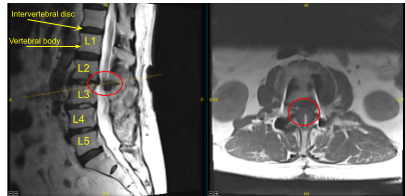

Este paciente había sido sometido previamente a una artrodesis instrumentada en una instalación externa en L3-5. Presentaron dolor en la parte anterior derecha del muslo y en la pierna posterior izquierda. Las imágenes mostraron una degeneración del segmento adyacente por encima y por debajo de su masa de fusión que se correlacionaba bien con sus síntomas.